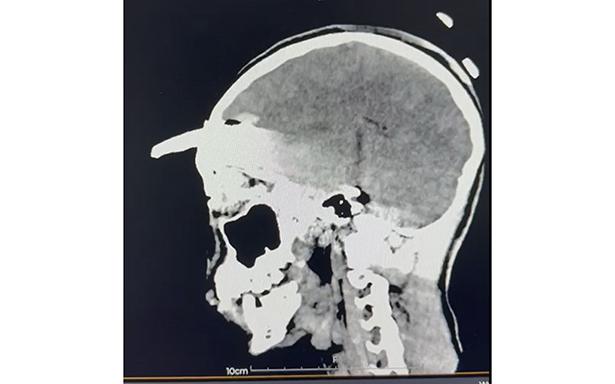

El Instituto Mexicano del Seguro Social (IMSS) en Yucatán logró un hecho médico sin precedentes al retirar, mediante una compleja cirugía, una herramienta agrícola -coa- de aproximadamente 30 centímetros incrustada en el cráneo de un adolescente de 15 años, procedimiento que permitió salvarle la vida.

Los estudios de imagen permitieron ubicar con precisión el objeto, mientras que el menor recibía tratamiento con antibióticos de amplio espectro para prevenir infecciones asociadas con el instrumento metálico.

Después de un análisis minucioso y una planeación quirúrgica, el doctor Ornelas González dirigió un procedimiento de cuatro horas que permitió retirar exitosamente el machete curvo sin afectar tejido cerebral, en una intervención que confirmó la pericia y capacidad del equipo médico.